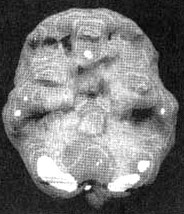

Мозг Линды. Результаты сканирования SPECT

Трехмерное изображение — активный мозг, вид сбоку.

До лечения: обратите внимание на выраженное усиление активности в поясной системе, в базальных ганглиях и в лимбической системе.

После лечение зверобоем. Активность в поясной системе, в базальных ганглиях и в лимбической системе нормализовалась.

Трехмерное изображение — активный мозг, вид снизу.